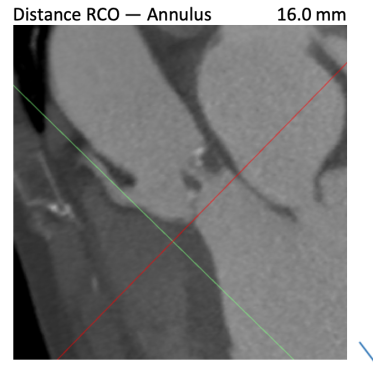

根据FEops报告上的左右冠脉CT截面得知RCA Height:16.0mm、LCA Height:16.0mm,冠脉阻塞风险比较低,通过植入前后的3D模型对比瓣叶形态可以进一步验证。

CT评估

瓣环直径:24.5mm,左室流出道直径:26.9mm

主动脉窦:27.3*30.2*32.1mm,STJ:27.2mm

升主动脉直径:31.2,心脏夹角:59度